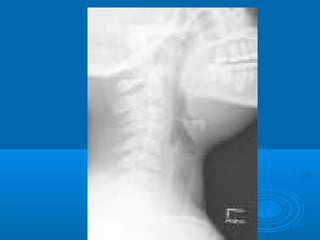

 RRxx ddee ccuueelllloo AA.. PP..

 SSee ppuueeddee rreeccoommeennddaarr uunnaa TTCC ddeell ccuueelllloo

ppaarraa ddeetteerrmmiinnaarr llaa eexxtteennssiióónn ddee llaa

iinnffllaammaacciióónn..

RRaaddiioollooggiiccaammeennttee ::

DDiiaaggnnóóssttiiccoo :: TT..AA..CC..